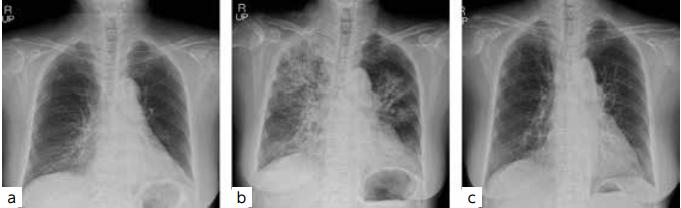

首次就诊5个月后,患者因红斑加重出现疼痛、行动困难,由救护车转至文章发表医院。临床表现为:躯干及四肢有带状鳞片样红斑,伴直径2mm小脓疱分散在整个身体上,形成一个充满脓液的海(图1a-c)。未见粘膜皮疹。

图1、a患者临床表现照片

c直径1-2毫米的小脓疱散布在全身,形成一个充满脓液的海

基于这些发现,患者诊断为OP合并RA。口服强的松龙以50mg /天的剂量开始治疗。增加强的松龙剂量后,不管是临床症状还是实验室检查结果都迅速好转。胸部X光片显示肺部病变明显改善(图5)。

图5、胸部X光检查

(a)入院时

(b)入院第7天

(c)入院第30天